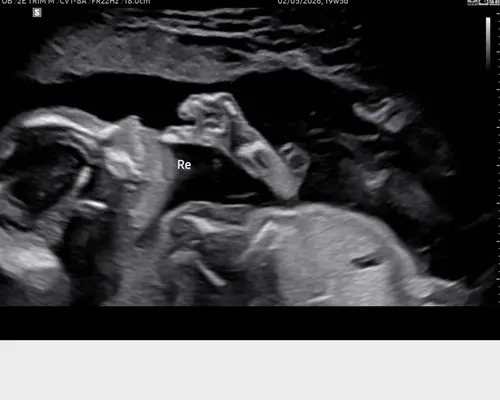

Ik ben ook 4 mei uitgerekend en had hem afgelopen dinsdag. Zeer uitgebreid naar het kindje kunnen kijken. Was er ongeveer 45min en zijn 63 foto's gemaakt 馃槄 Gelukkig gaat alles goed馃榿

Hier was ook alles goed met onze baby boy 馃┑馃槏